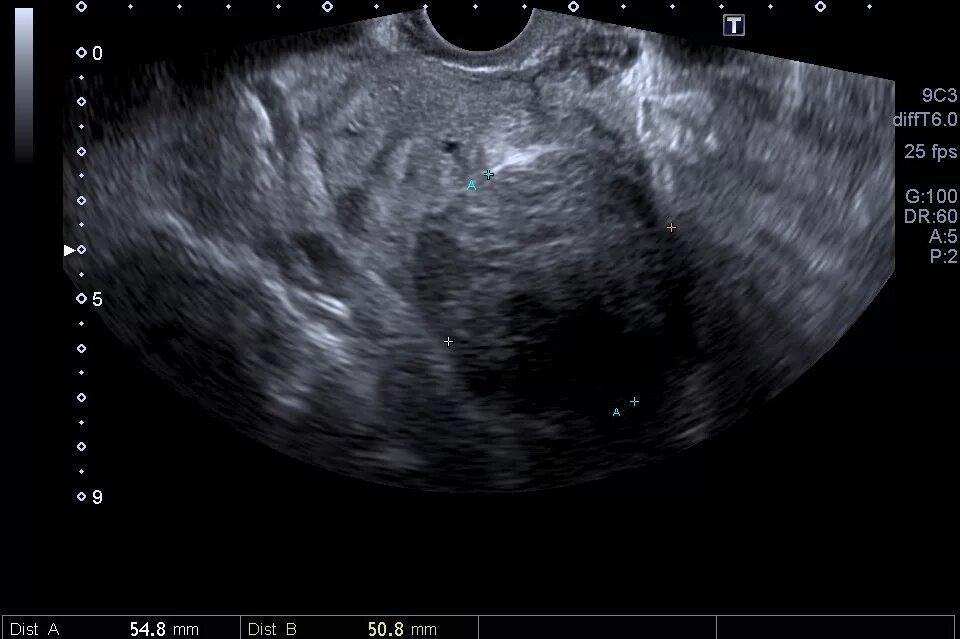

Полип эндометрия в матке причины